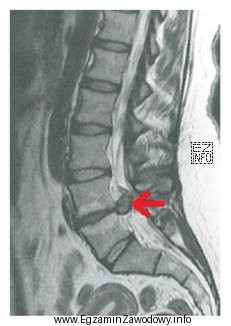

PYTANIE NR 25.

Na obrazie MR kręgosłupa lędźwiowego strzałką wskazano

A.

osteofit na poziomie L2-L3

B.

osteofit na poziomie L4-L5

C.

przepuklinę na poziomie L2-L3

D.

przepuklinę na poziomie L4-L5